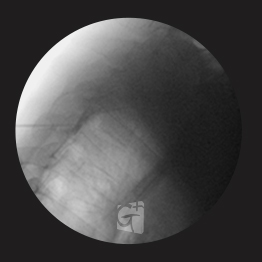

경추 신경성형술

-

경추 좌측 2번 신경절

경막외 카테터 삽입 -

척추관 안쪽으로 진입하여 약물 주입

-

원인부위 염증 제거 및 유착 박리

-

유착박리로 추간공 확보 신경 압박 감소

-

척추관에서 약물이 퍼져나오는 모습

-

목 신경 전체를 효과적으로 치료